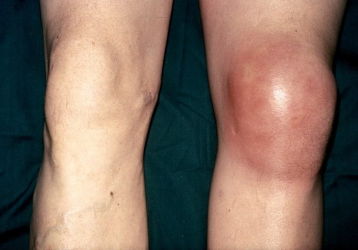

Что делать, если опухло колено без ушиба и болит: диагнозы и способы лечения

Если опухло колено без ушиба и болит нужно установить причину. Перечень диагнозов ведущих к отеку мягких тканей. Что делать с опухолью.